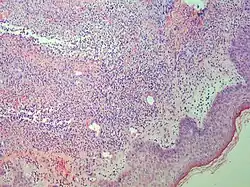

Studies show a moderate neutrophilia (less than 50%), elevated ESR (greater than 30 mm/h) (90%), and a slight increase in alkaline phosphatase (83%). Skin biopsy shows a papillary and mid-dermal mixed infiltrate of polymorphonuclear leukocytes with nuclear fragmentation and histiocytic cells. The infiltrate is predominantly perivascular with endothelial-cell swelling in some vessels, but vasculitic changes (blood clots; deposition of fibrin, complement, or immunoglobulins within the vessel walls; red blood cell extravasation;inflammatory infiltration of vascular walls) are absent in early lesions.Perivasculitis occurs secondarily, because of cytokines released by the lesional neutrophils. True transmural vasculitis is not an expected finding histopathologically in SS.

Sweet described a disease with four features: fever; leukocytosis; acute, tender, red plaques; and a papillary dermal infiltrate of neutrophils. This led to the name acute febrile neutrophilic dermatosis. Larger series of patients showed that fever and neutrophilia are not consistently present. The diagnosis is based on the two constant features, a typical eruption and the characteristic histologic features; thus the eponym "Sweet's syndrome" is used.